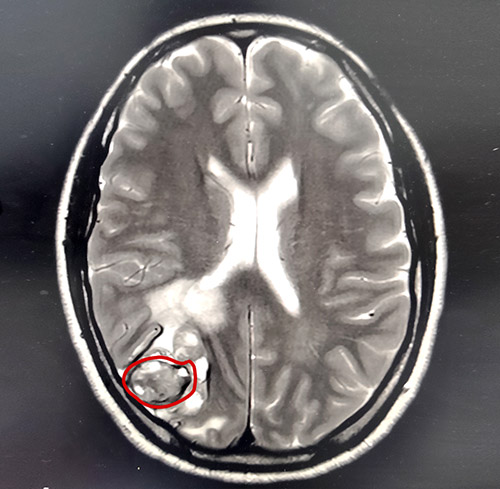

胡女士就是不信这个邪,经多方打听后胡女士辗转来到上海蓝十字脑科医院。在蓝十字脑科医院进行了仔细全面的体检,影像检查提示:左足跟黑色素瘤切除术后,患者颅脑右侧枕叶皮髓质交界处高密度团块伴周围脑实质水肿,考虑为转移瘤。身体其他部位未见明显转移灶。

▲MRI提示右侧顶枕叶皮髓质交界处占位